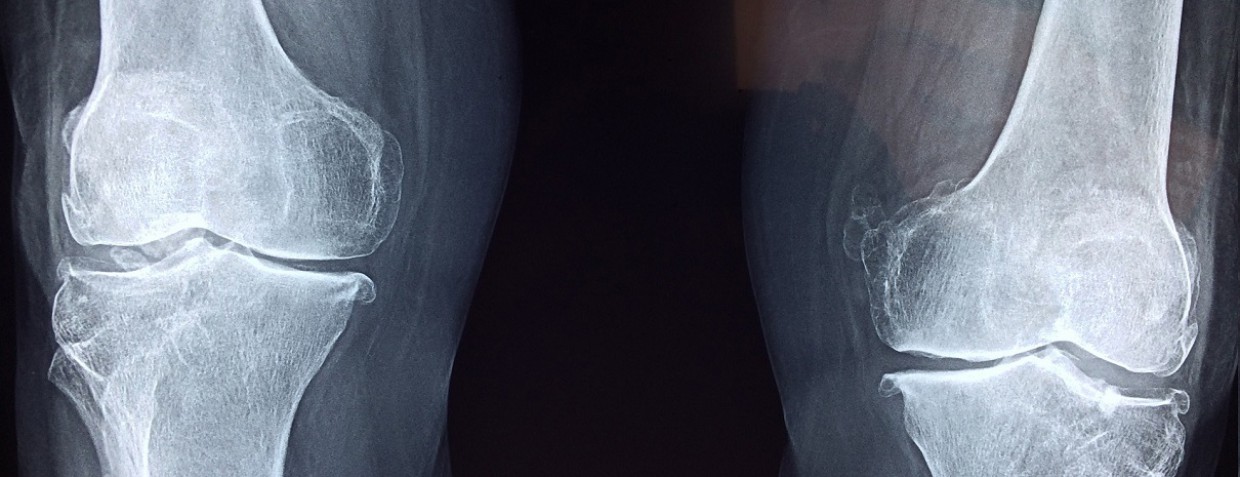

A rendelésre kérjük a panaszos területről készült röntgenfelvételeit, korábbi leleteit hozza magával!

Térd panaszok esetén:

•     Összehasonlító terheléses (álló helyzet) AP és oldal irányú térd röntgenfelvételek